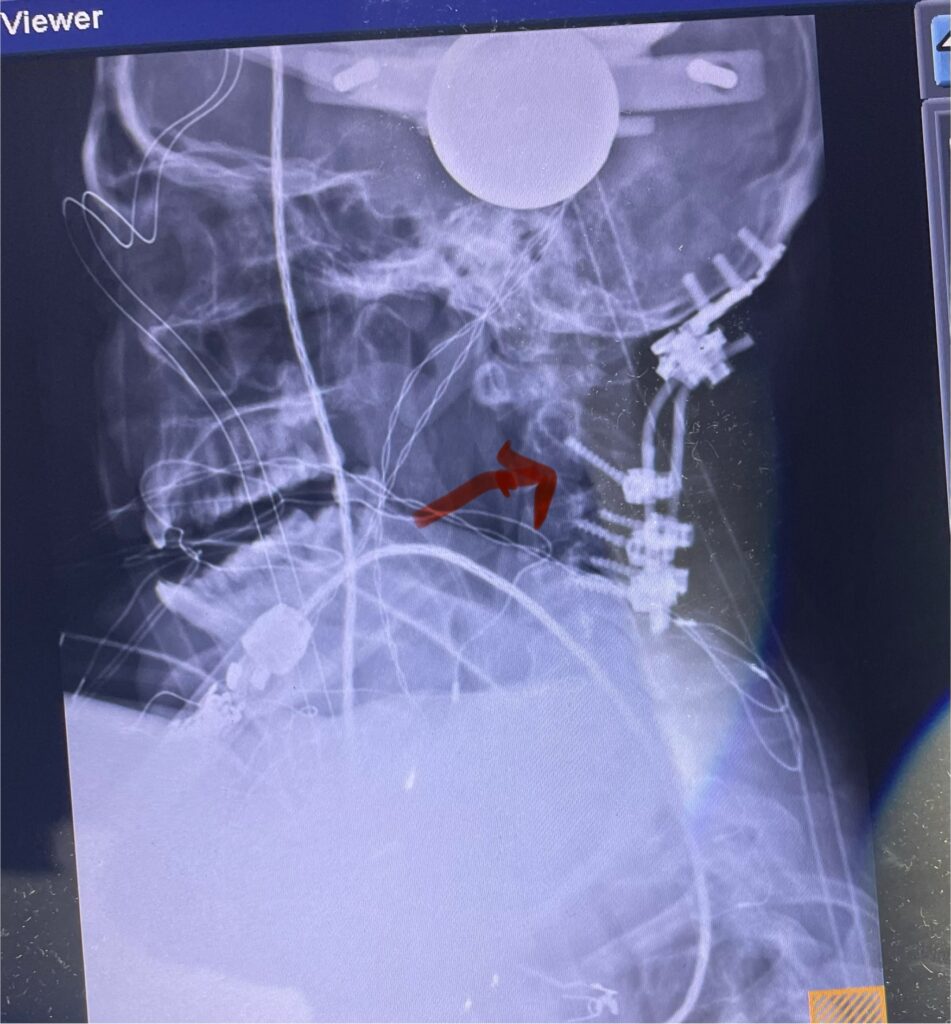

Here is a tough case: This is a 72 year-old male who presented with several months of progressive neck pain without symptoms of the arms or legs. […]